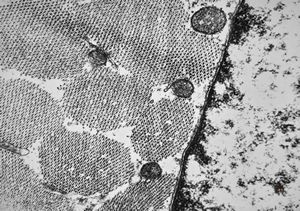

M,56y. | amyloidosis - tendon